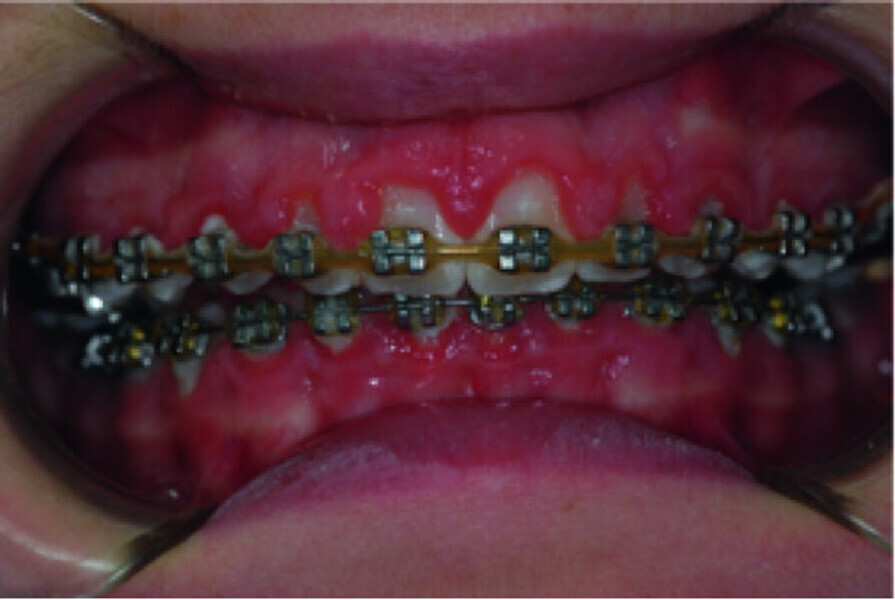

Use of diode laser in the treatment of gingival enlargement during orthodontic treatment